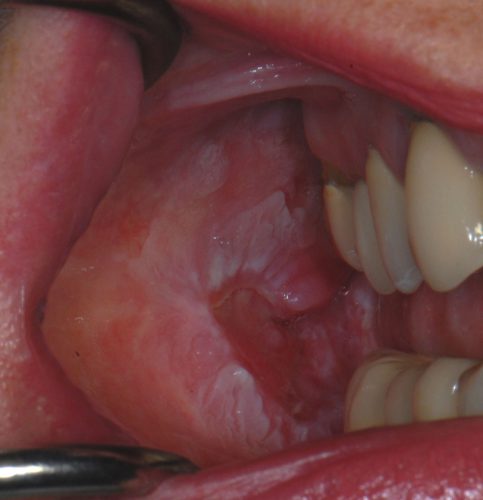

Being familiar with early warning signs can make a life-saving difference. Symptoms to look out for include:

- Persistent ulcers that do not heal within two weeks

- Red or white patches in the mouth

- Unexplained lumps or thickening of tissue